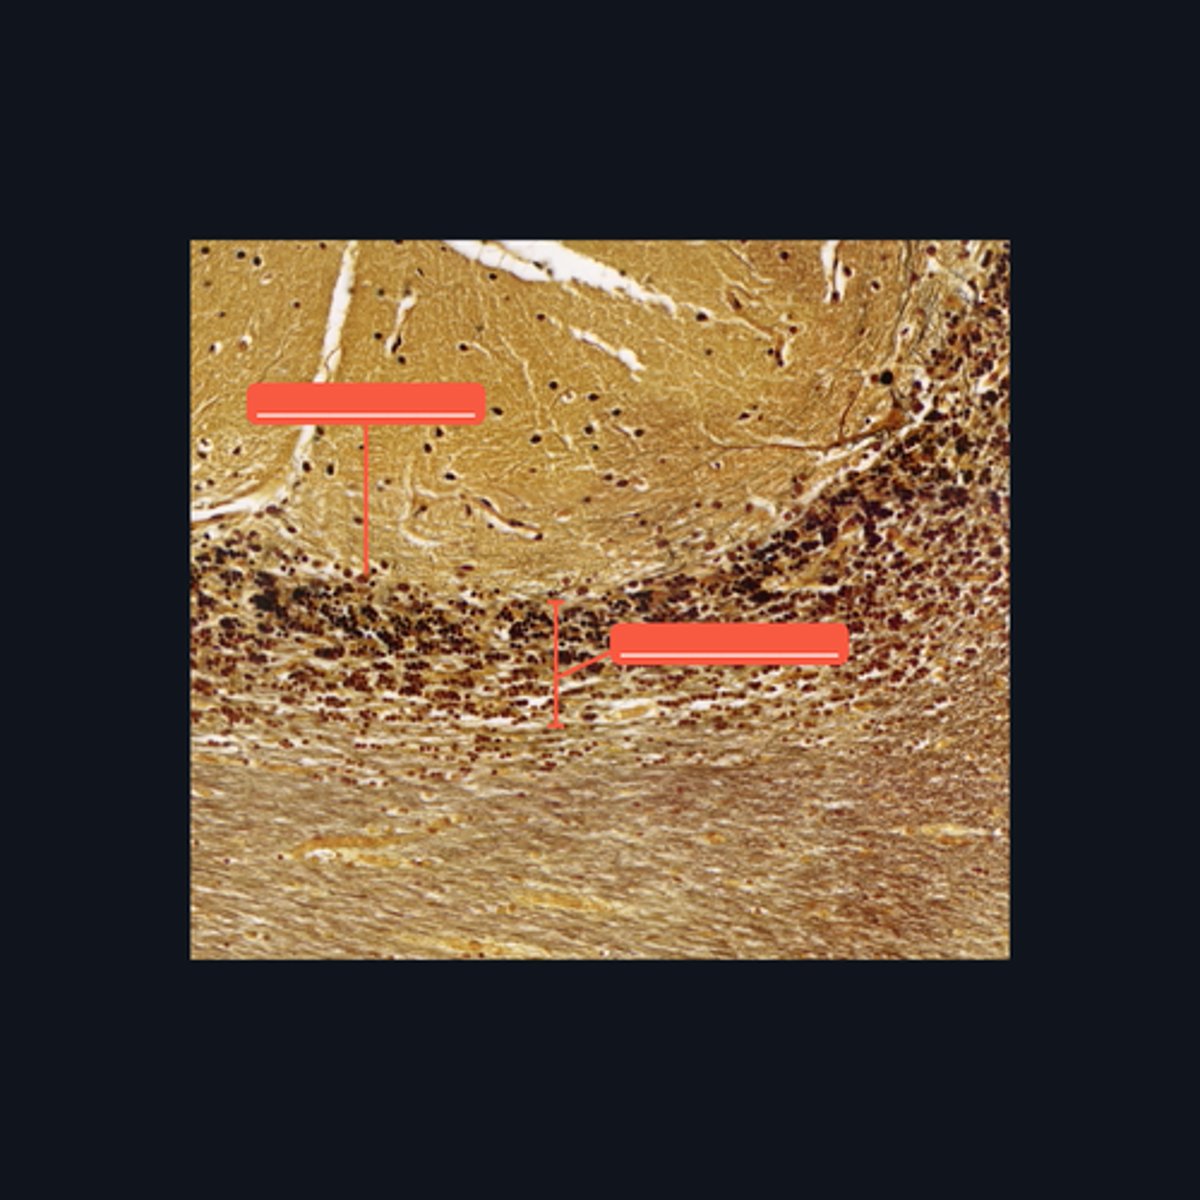

Gray Matter

Identify the pointed region in the spinal cord

(1) Ventral Horn, (2) Dorsal Horn

Identify the pointed regions of the gray matter of the spinal cord

Gray Matter (When looking at speciemen from the brain, all areas in the periphery are considered Gray Matter)

Identify the pointed region in the Cerebellum

"cell bodies, dendrites, proximal portions of the axons, and neuroglial cells"

Enumerate the structures found in the pointed region